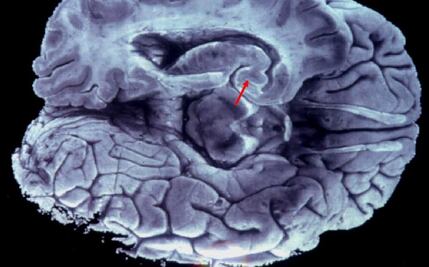

La investigación demuestra que la misma región cerebral puede motivar un comportamiento aprendido y suprimir ese mismo comportamiento